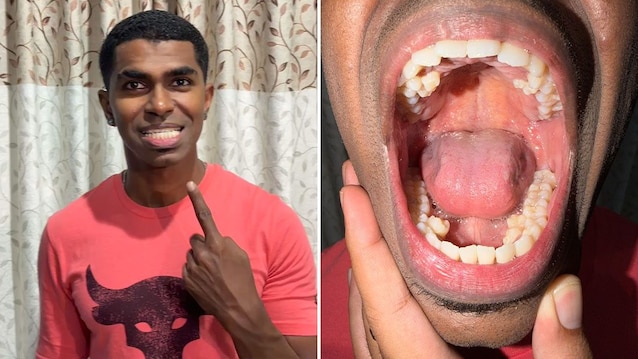

Among the many Guinness World Records linked to the human body – from the woman with the longest hair to the tallest man in history – there is also one that concerns the smile: Prathab Muniandy it’s thereman with the most teeth in the worldin total 42, or 10 more compared to average of other human beings.

The most peculiar aspect of this story is that Muniandy, Malaysian citizen who works as an engineer in the oil industry, he noticed of this particularity only in 2021, when he was over 30 years old: as reported on the official Guinness World Records page, he realized he had more teeth than others during a family event.

At that point, he and his relatives would realize they had a total 38 teeth: the subsequent dental panoramic would then confirm the presence of another 4 teeth ready to erupt. His story was verified in 2023, when two more dental visits confirmed the presence of 42 teeth total.

Fortunately, the 10 extra teeth did not cause any particular problems and, for this reason, they were not removed from him: Muniandyin fact, holds the record as the man with the greatest number of teeth that everyone still has. The women’s record, however, is in the hands of Kalpana Balanan Indian woman who owns 38.